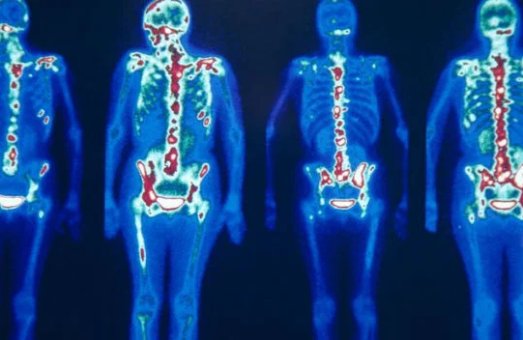

На відміну від більшості методів, які показують лише будову органу, радіонуклідна діагностика дозволяє оцінити, як він працює.

Пацієнтові вводять спеціальну речовину, в складі якої є радіонуклід, що підбирається індивідуально для певного органу чи тканини. Цей радіонуклід випромінює гамма-кванти, які фіксуються сучасною апаратурою. Важливо підкреслити: променеве навантаження при цьому у 100 разів менше, ніж при звичайному рентгені. Це робить метод безпечним навіть для ослаблених пацієнтів. У результаті лікар отримує зображення, які відображають не лише структуру органу (як при УЗД або МРТ),а й його функціонування на молекулярному рівні. Завдяки цьому патологічні процеси можна виявити на 6–9 місяців раніше, ніж іншими методами. Чим раніше встановлений діагноз — тим більше шансів на успішне лікування.

Використовуються сучасні радіонуклідні методики, що дозволяють виявити навіть приховані захворювання на початковому рівні.